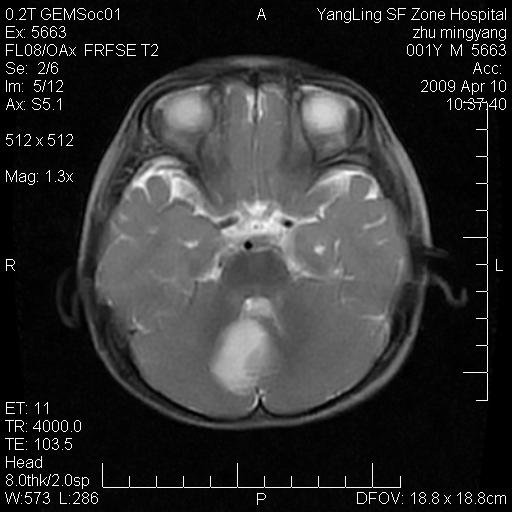

患者:1岁半,两天前外伤收住我院,ct检查小脑占位

考虑星形细胞瘤,建议增强

髓母细胞瘤或血管母细胞瘤,增强后可以鉴别;影像资料见 <。鱼博浪老师的《中枢神经系统ct与mr鉴别诊断》 小脑部肿瘤章节。

髓母细胞瘤或血管母细胞瘤!支持!

支持考虑髓母细胞瘤

考虑----髓母细胞瘤可能性大

考虑髓母细胞瘤或室管膜瘤。

支持髓母细胞瘤。

考虑髓母细胞瘤。

考虑髓母细胞瘤或星形细胞瘤

考虑髓母细胞瘤.

考虑髓母细胞瘤可能性大。

小脑肿瘤.考虑髓母细胞瘤可能.

就病灶部位及临床资料首先考虑髓母.